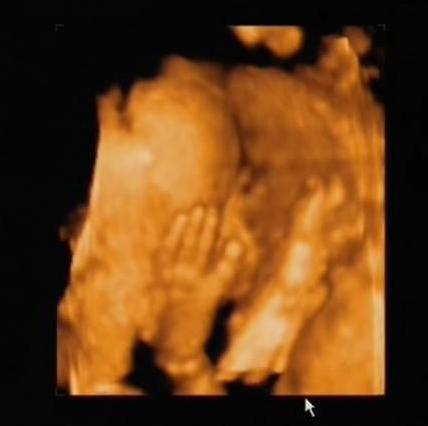

Láttuk a kis hercegnőnket! Ugyanis megint kicsi lányt látott a doki. Mostmár az esélyünk elérte a 90%-ot! Én annyira boldog vagyok!

És képzeljétek, amig néztük őt uh-on, iszogatott a magzatvízből.

Nyitogatta a kicsi száját, és a doki még a nyelőcsövét is megmutatta, hogy látszódik a folyadék ahogy nyel...

És (Titim rád gondoltam, még a könnyem is kijött) láttam a kicsi száját, az alsó-felső ajkát, mindenét...

Persze nehogy azt higyjétek, hogy élvezte a kukucskálást. Megmutatta a lényeget, de aztán elfordult, eltakarta magát... Nem is akárhogy!!!

Rakok fel képeket, remélem látszódni fog rajta minden!

A magzatvizet iszogatom...

A lábacskám...

Na, mostmár elegem van... (két kézzel takarja az arcát)

Hagyjatok már!!! (két kéz és egy láb látható a képen, úgy bújt el a drága